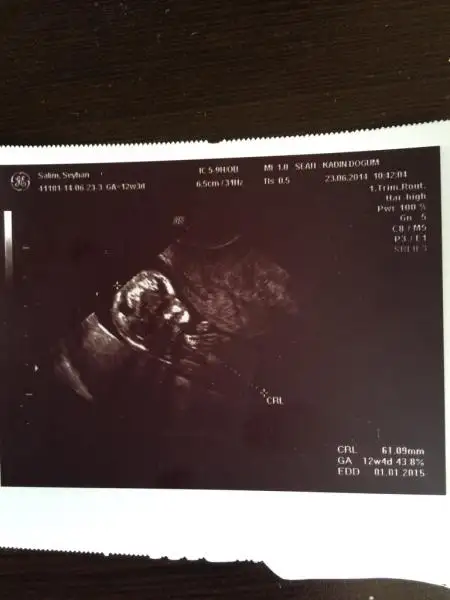

Fananaycım bunada yorum yapabılırmısın bu arkadasımın bebegının fotosu

Canım beceremiyorum Ben yaa ;) bu bebekte nubu göremedim bile hiç:O bilion bir de kendi bebeğime kız dedim erkek çıktı tutmuyor benm tahminler :))